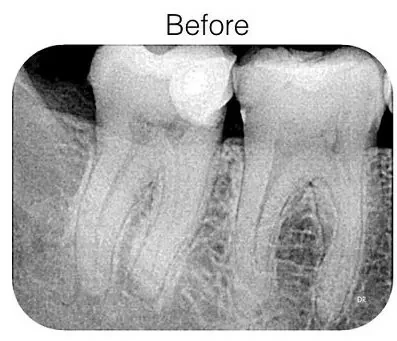

Root Canal Treatment / Rotary Endodontics At Shinas Dental Clinic Barka.

Root Canal Treatment Is A Procedure Used To Treat Infected Or Damaged Tooth Pulp, Which Is The Inner Part Of The Tooth Containing Nerves And Blood Vessels. Shinas Dental Clinic We Offer Advanced Rotary Root Canal Therapy To Effectively And Efficiently Treat Root Canal Infections And Save Damaged Teeth. During The Procedure, The Dentist Uses Rotary Instruments To Clean And Shape The Root Canal System Thoroughly. This Advanced Technology Allows For More Precise Cleaning And Shaping Of The Canals, Leading To Better Outcomes And Reduced Treatment Time. Rotary Root Canal Therapy At Shinas Dental Clinic Offers Several Benefits: Efficient Cleaning: Rotary Instruments Enable Thorough Cleaning Of The Root Canal System, Removing Infected Tissue And Bacteria Effectively. Precise Shaping: The Instruments Allow For Precise Shaping Of The Canals, Ensuring Better Sealing Of The Tooth After Treatment. Reduced Discomfort: The Efficient And Precise Nature Of Rotary Root Canal Therapy Can Lead To Reduced Post-Operative Discomfort For Patients. Preservation Of Natural Teeth: By Effectively Treating Infections And Saving Damaged Teeth, Rotary Root Canal Therapy Helps Preserve Natural Teeth And Avoid The Need For Extraction. With Our Experienced Team And Advanced Technology, We Provide High-Quality Rotary Root Canal Therapy At Shinas Dental Clinic, Ensuring Optimal Outcomes And Improved Oral Health For Our Patients.